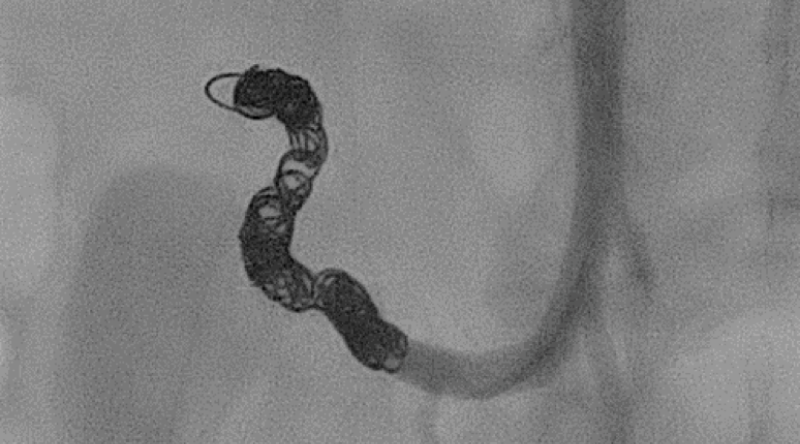

In seltenen Fällen kann es zu einer akuten nicht-zirrhotischen Thrombose von Pfortader und anderen splanchnischen Thrombosen kommen. Diese Situation ist äußerst bedrohlich und sollte umgehend an einem Zentrum behandelt werden. Das CCB hat als eines von wenigen Zentren in Deutschland die Möglichkeit solche Thrombosen interventionell mit Thrombaspiration und lokaler Thrombolyse zu behandeln.

Auch chronische Thrombosen der splanchnischen Gefäße können bei ausgewählten Patienten am CCB rekanalisiert werden.

Für diese Interventionen arbeiten wir eng mit den Kollegen der Klinik für Diagnostische und Interventionelle Radiologie zusammen.